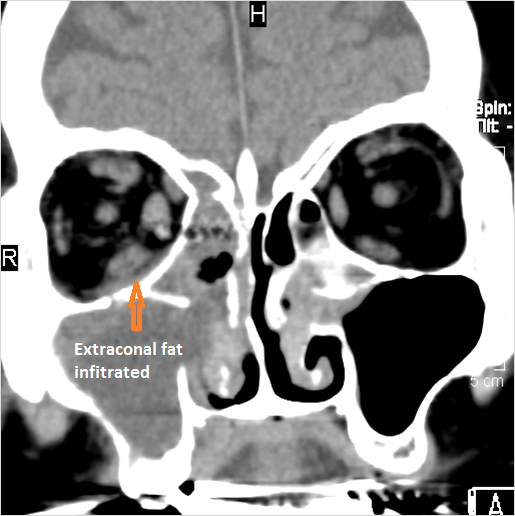

The extraconal orbital fat surrounding the infraorbital vascular bundle is infiltrated